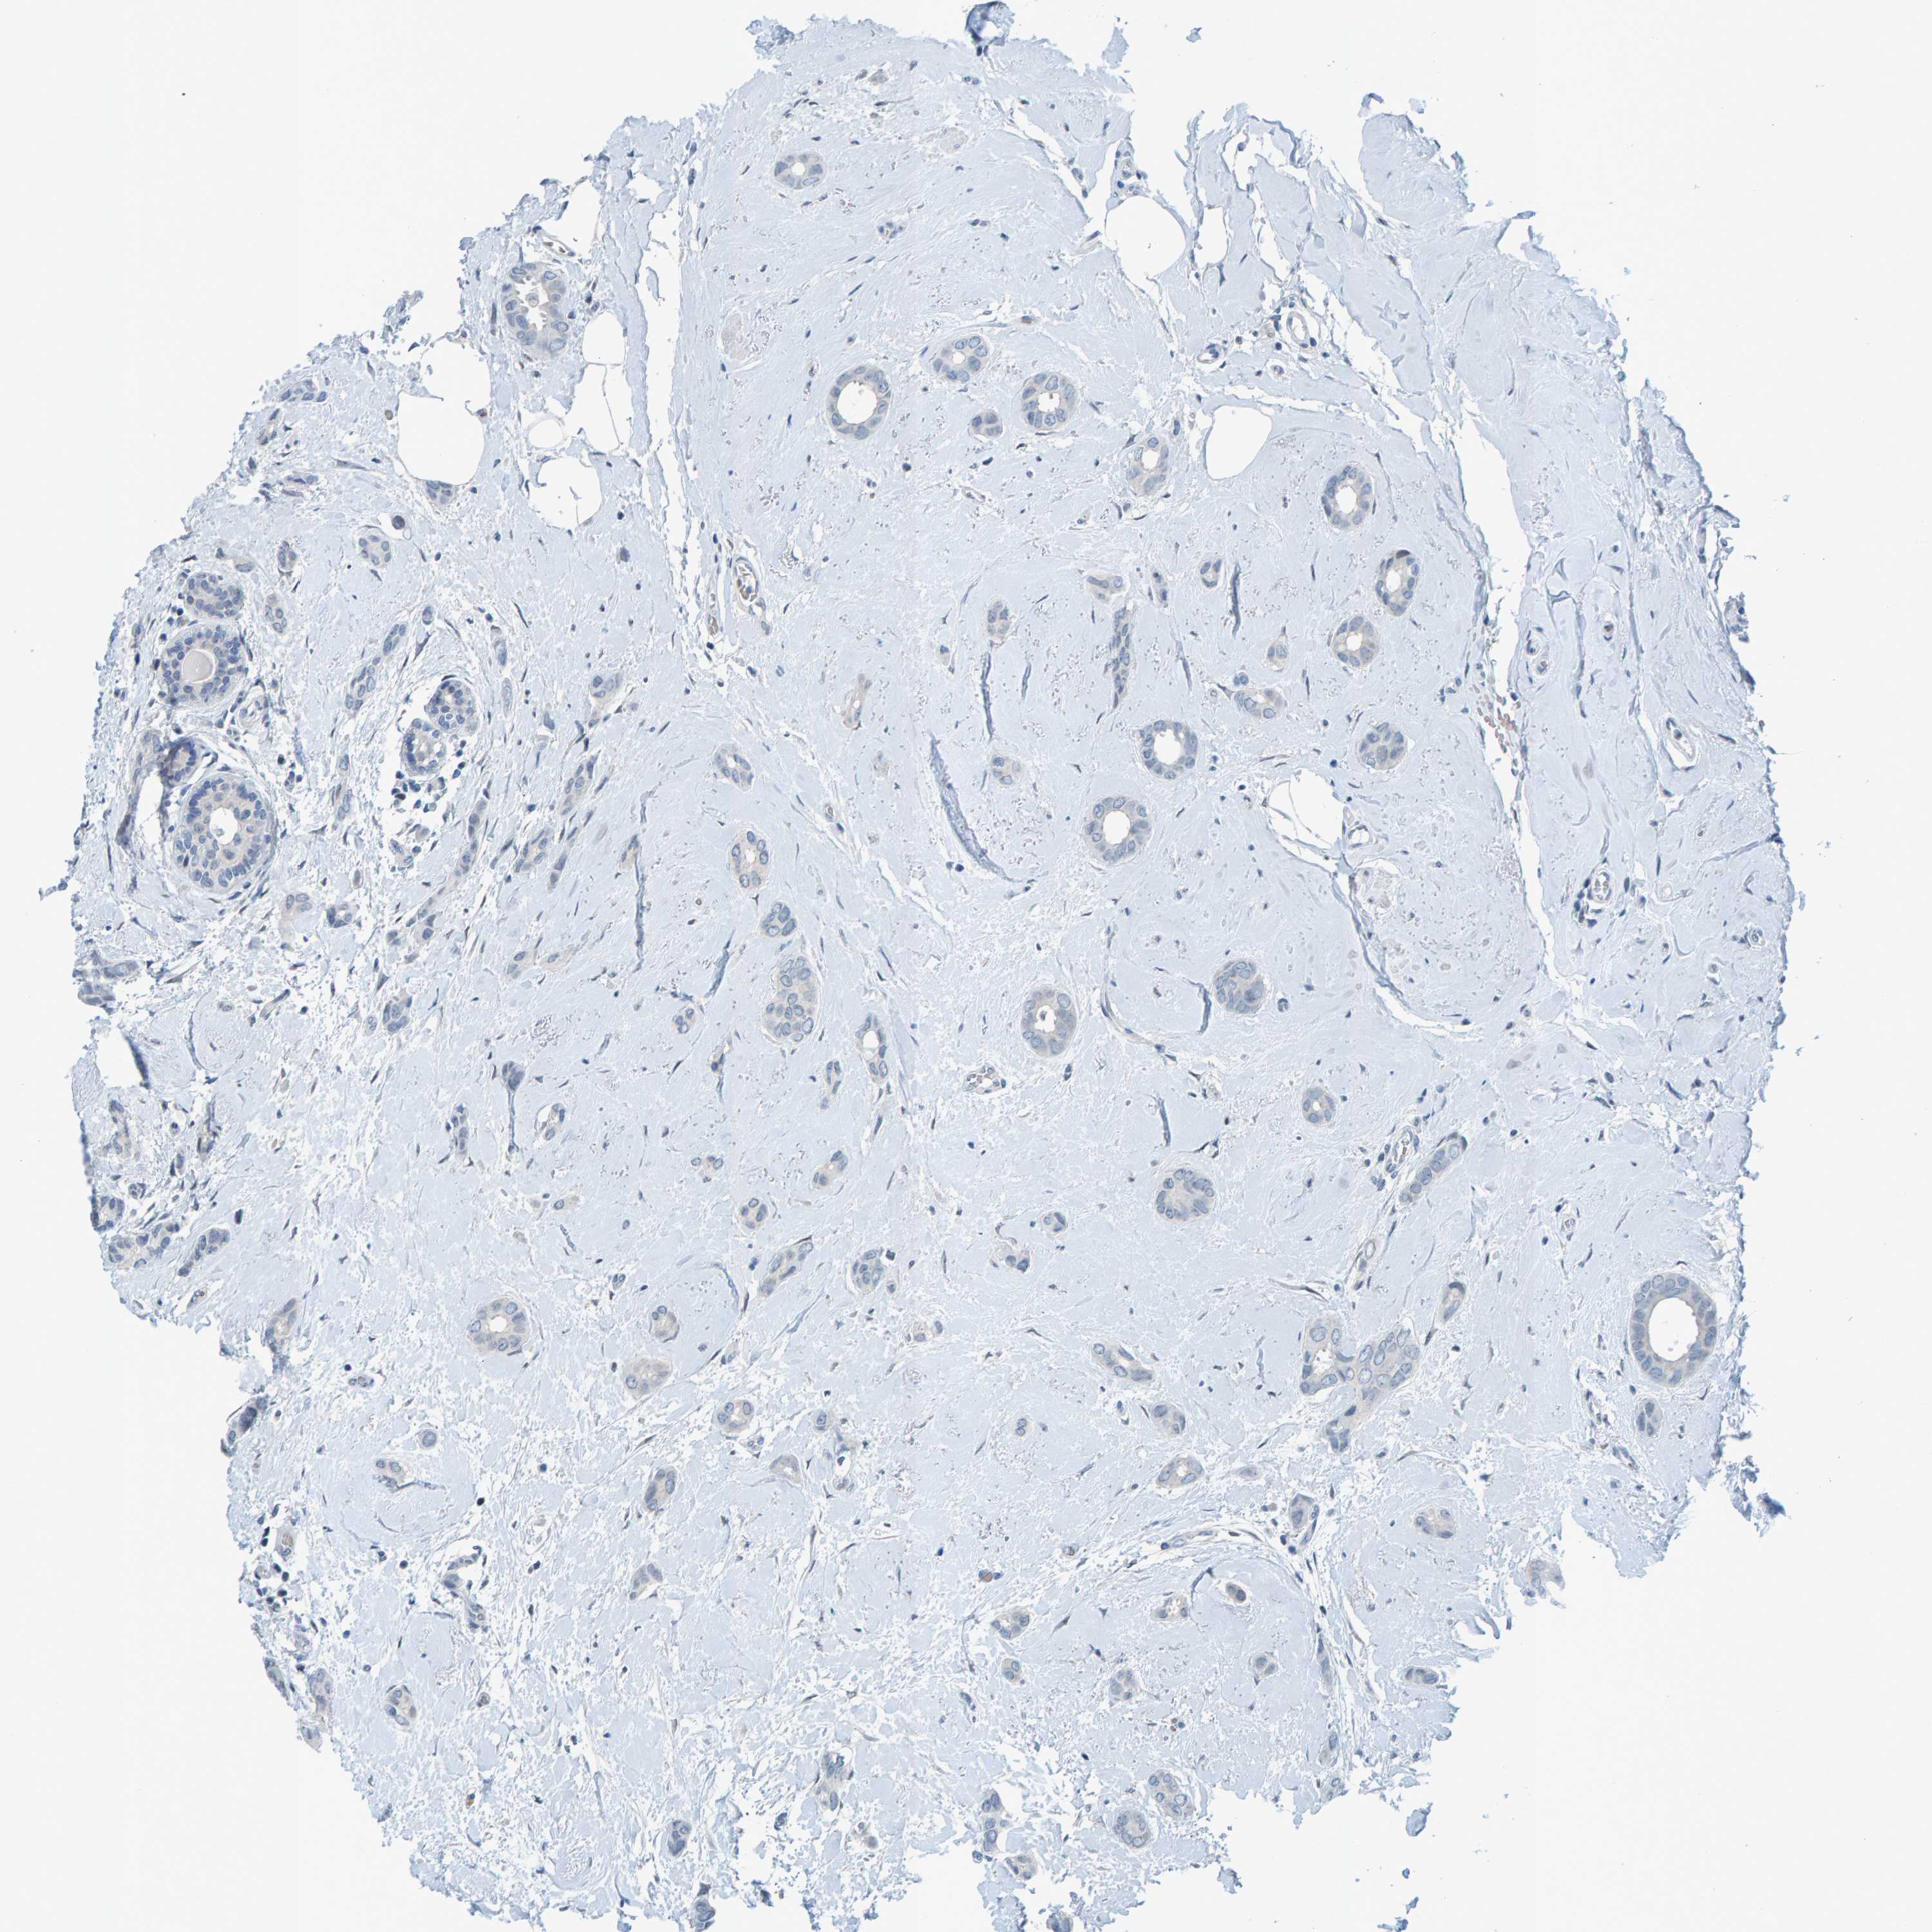

BRCA TCGA BRCA VALIDATION PROTEIN EXPRESSION

ANTIBODIES

AND

VALIDATION